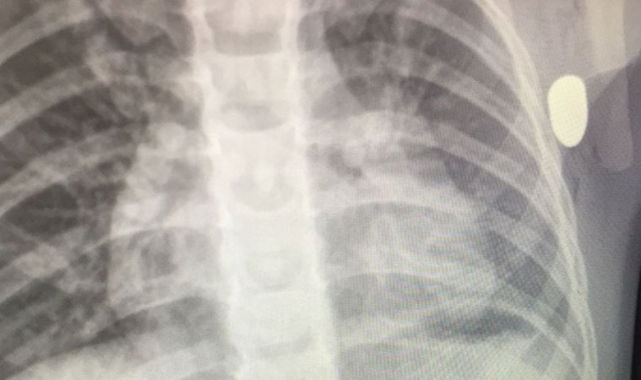

Durumu ağırlaşan Aydemir, sevk edildiği kent merkezindeki Eğitim ve Araştırma Hastanesi'nde ameliyata alındığı öğrenildi. Tedavisi süren Aydemir'in maganda kurşununun hedefi olduğu, yorgun merminin de sol kolunun alt kısmından girip, göğsüne saplandığı tespit edildi. Soruşturma başlatan polis, silahı ateşleyen kişinin tespit edilmesi için çalışma başlattı.